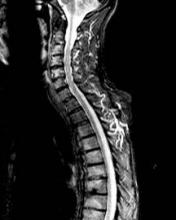

Courtesy of Dr. Pedro Machado

STIR magnetic resonance image of the upper spine of a patient with ankylosing spondylitis, showing inflammatory lesions (bright signal) in multiple vertebral units.